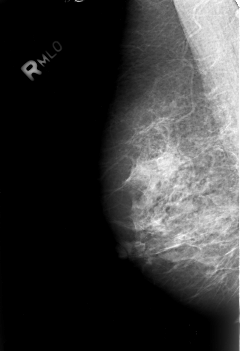

B_3007_1.RIGHT_MLO

RIGHT_MLO LINES 4208 PIXELS_PER_LINE 2872 BITS_PER_PIXEL 12 RESOLUTION 50 NON_OVERLAY